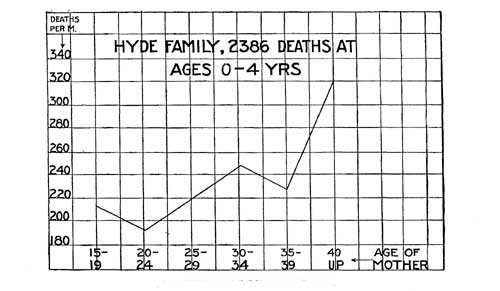

| 44. Influence of Mother's Age | 347 |